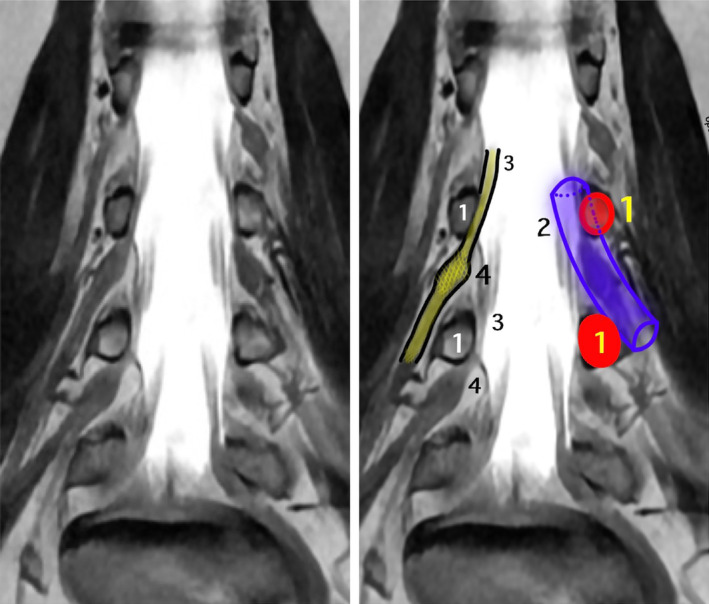

Discussion: Percutaneous procedure targeting the DRG for the treatment of chronic pain requires preoperative planning independent to the study of the etiology of pain. The DRG should be typified using magnetic resonance imaging. We propose a preoperative evaluation scale based on four specific items: A-position in the vertebral canal, B-position of the DRG within the foramen, C-number of ganglia in the root, and D-ratio (proportion) of foramen/DRG.

Abstract Image